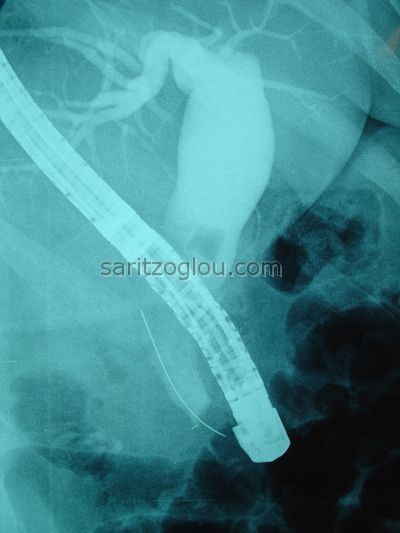

Χοληδοχολιθίαση. Έγινε λιθοτριψία και τοποθέτηση pig-tail stent Aαπεικόνιση υπολοιπόμενου λίθου εντός του πόρου.